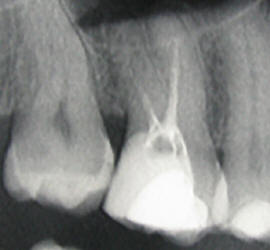

V zelo redkih primerih, endodontsko zdravljenje ne more biti uspešno izvedeno zaradi zelo tenkih in ukrivljenih kanalov ali slabega prejšnjega endodontskega zdravljenja

Slabo endodontsko zdravljenje

Nekateri od teh primerov se uspešno rešujejo z revizijo (ponovno čiščenje in razkuževanje kanalov) ali z apikotomijo (kirurško odstranitvijo vrška korenine).

Po ponovnem zdravljenju koreninskih kanalov